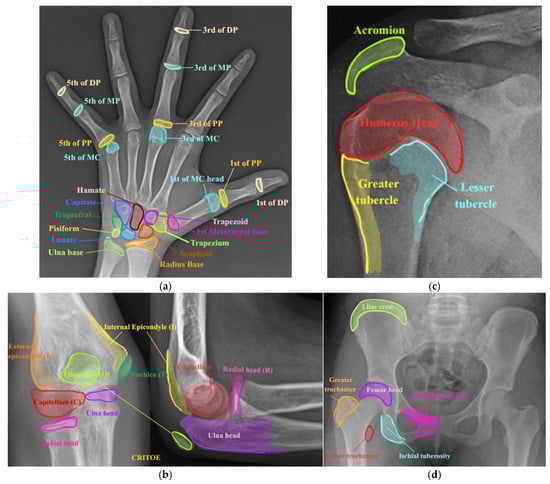

Figure 7 clarifies the anatomy of the multiple joints, as validated by the forensic expert, to ensure forensic accuracy, especially regarding ossification centers and joint margins relevant to skeletal age estimation. Specifically, class 1 represents individuals from infancy to toddlerhood (ages: 0.1 to 4 years), referred to as the Indian Medicolegal Infant-Toddler (IMIT). Class 2 represents individuals from 5 to 7 years, labeled as Indian Medicolegal Child (IMC); class 3 represents individuals from 8 to 12 years, labeled as Indian Medicolegal Pre-Adolescent (IMPA); class 4 represents individuals from 13 to 14 years, labeled as Indian Medicolegal Pre-Teen (IMPT); class 5 represents individuals from 15 to 18 years, labeled as Indian Medicolegal Teen (IMT); class 6 represents individuals from 19 to 21 years, labeled as Indian Medicolegal Young Adult (IMYA), while class 7 encompass individuals aged 21year and older, labeled as Indian Medicolegal Adult (IMA) [1].

Figure 7.

The appearance and fusion state of various joint anatomies (a) Wrist (IMIT: capitate, hamate, triquetral, lunate, radius base and 1st MC head and base, 3rd MC head, 5th MC head, 1st PP, 3rd PP, 5th PP, 3rd MP, 5th MP, 1st DP, and 3rd DP (appearance); IMC: appearance of trapezoid, trapezium, scaphoid, and ulna base, 5th DP (appearance); IMPA: pisiform (appearance), MC’s, PP’s, MP’s, and DP’s (non-union with separate epiphysis); IMPT: MC’s, PP’s, MP’s, and DP’s (partial union); IMT: MC’s, PP’s, MP’s, and DP’s (complete union); IMYA: nil; IMA (above): nil); (b) Elbow (IMIT: capitellum (appearance); IMC: medial/internal epicondyle and radius head (appearance); IMPA: trochlea, lateral/external epicondyle, and ulna head (appearance); IMPT: capitellum, trochlea, and lateral epicondyle (conjoint epiphysis); olecranon (appearance); IMT: medial epicondyle, radius head, and ulna head (conjoint epiphysis); olecranon (fuses with shaft of ulna seen in lateral view); IMYA: nil; IMA: nil); (c) Shoulder (IMIT: humerus head, greater tubercle (appearance); IMC: lesser tubercle (appearance); IMPA: humerus head, greater tubercle, and lesser tubercle (conjoint epiphysis); IMPT: acromion process (appearance); IMT: acromion process (appearance and conjoint epiphysis with the scapular); IMYA: humerus head, greater tubercle, and lesser tubercle (conjoint epiphysis fuses with shaft of humer); IMA: nil); (d) Pelvis (IMIT: femur head and greater trochanter (appearance); IMC: ischiopubic ramus (fusion); IMPA: lesser trochanter (appearance); IMPT: lesser trochanter and iliac crest (appearance); IMT: ischial tuberosity (appearance), femur head, greater trochanter, and lesser trochanter (fusion); IMYA: lliac crest and ischial tuberosity (fusion); IMA: nil) [1].